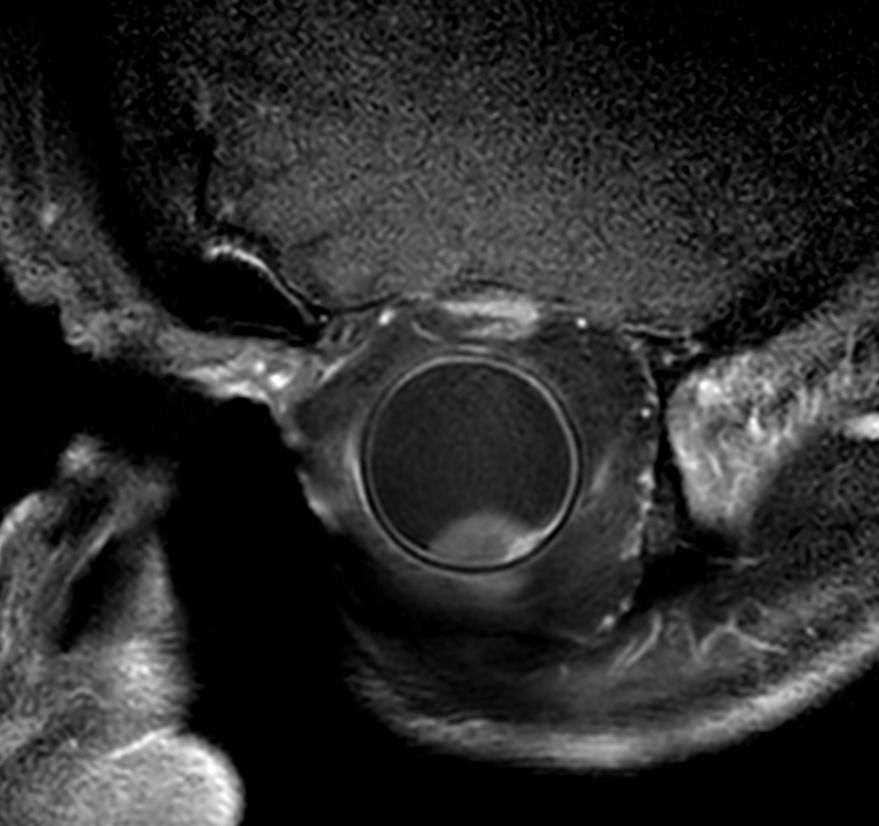

4 different 3D isotropic sequences, T1W with and without fat saturation, T2W and T1W fat saturation post-contrast are used to evaluate the tumor prior to treatment. Isotropic sequences are used to allow for good quality multiplanar reconstruction corresponding to the location of the tumor; as the tumor can be located anywhere in the eye, optimal visualization often requires an assessment of different oblique planes, which is facilitated by the 3D isotropic sequences. The pre-contrast sequences help evaluate the tumor size and location and the post-contrast sequence provides additional information such as identifying tumor that has seeped through the sclera behind the eye and differentiating tumor vs associated retinal detachment.

Higher in-plane resolution 2D sequences are used to better evaluate the tumor and screen for infiltration to the adjacent structures, which can have direct therapeutic consequences.